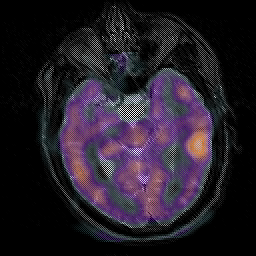

Subacute Stroke, overlay -- Slice #10

[Home][Help][Clinical] Slice 10